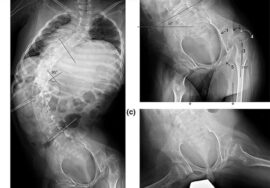

يتم تصميم الحزام بشكل مخصص لكل مريض بناءً على زاوية الاعوجاج (زاوية كوب)، ومكان الانحناء، وسن المريض، ومستوى نمو العظام.

ويُنصح باستخدام الحزام خصوصًا عندما تكون زاوية الانحناء بين 20 و40 درجة، ولم يكتمل بعد النضج العظمي.

ويتم تقييم النتائج بشكل دوري من خلال الأشعة السينية لقياس زاوية الانحناء (زاوية كوب).

إذا أظهرت المتابعة أن الانحناء لم يتفاقم، فهذا يعني أن العلاج بالحزام ناجح، ويستمر حتى اكتمال النمو العظمي.